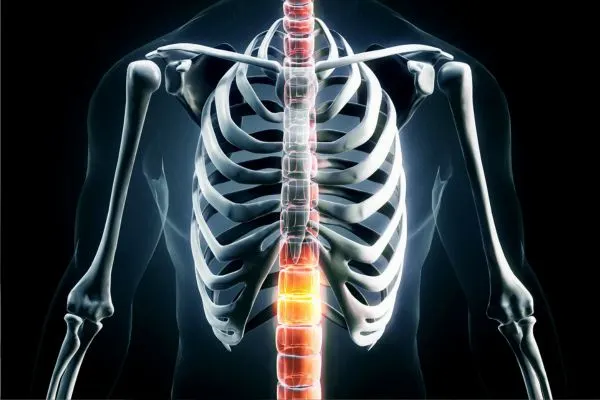

Overview of Spinal Tuberculosis

Spinal tuberculosis occurs when infection affects the bones of the spine, leading to weakening and structural changes over time. Symptoms may appear slowly and are sometimes mistaken for routine back discomfort. At SMH Prime Ortho, emphasis is placed on recognising subtle warning signs and understanding how infection-related changes influence spinal alignment and function.